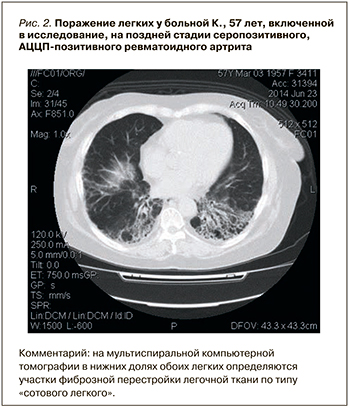

По данным нашего исследования, у АЦЦП-позитивных пациентов достоверно чаще встречались ревматоидные узелки, а в отношении других МСКТ-признаков интерстициального поражения различия оказались статистически незначимыми. Факт того, что большинство различий оказалось недостоверным, также можно объяснить величиной выборки. Однако, на наш взгляд, полученные результаты в большей степени связаны с особенностью дизайна исследования и статистического анализа данных. Это обусловлено тем, что в цитируемых работах [6, 10, 12] осуществлялось сравнение титров АЦЦП у пациентов с клинически манифестированным интерстициальным поражением легких без учета субклинических вариантов, в то время как последние наблюдаются гораздо чаще – у 70–80% больных [11]. Судя по всему, именно это обстоятельство вызывает искажение данных статистического анализа. Не вызывает сомнений, что высокий титр АЦЦП ассоциирован с более тяжелым течением поражения легких [6, 12], но в то же время низкие цифры АЦЦП не исключают развитие субклинического интерстициального поражения легких (рис. 1 и 2).

По данным нашего исследования, у АЦЦП-позитивных пациентов достоверно чаще встречались ревматоидные узелки, а в отношении других МСКТ-признаков интерстициального поражения различия оказались статистически незначимыми. Факт того, что большинство различий оказалось недостоверным, также можно объяснить величиной выборки. Однако, на наш взгляд, полученные результаты в большей степени связаны с особенностью дизайна исследования и статистического анализа данных. Это обусловлено тем, что в цитируемых работах [6, 10, 12] осуществлялось сравнение титров АЦЦП у пациентов с клинически манифестированным интерстициальным поражением легких без учета субклинических вариантов, в то время как последние наблюдаются гораздо чаще – у 70–80% больных [11]. Судя по всему, именно это обстоятельство вызывает искажение данных статистического анализа. Не вызывает сомнений, что высокий титр АЦЦП ассоциирован с более тяжелым течением поражения легких [6, 12], но в то же время низкие цифры АЦЦП не исключают развитие субклинического интерстициального поражения легких (рис. 1 и 2).